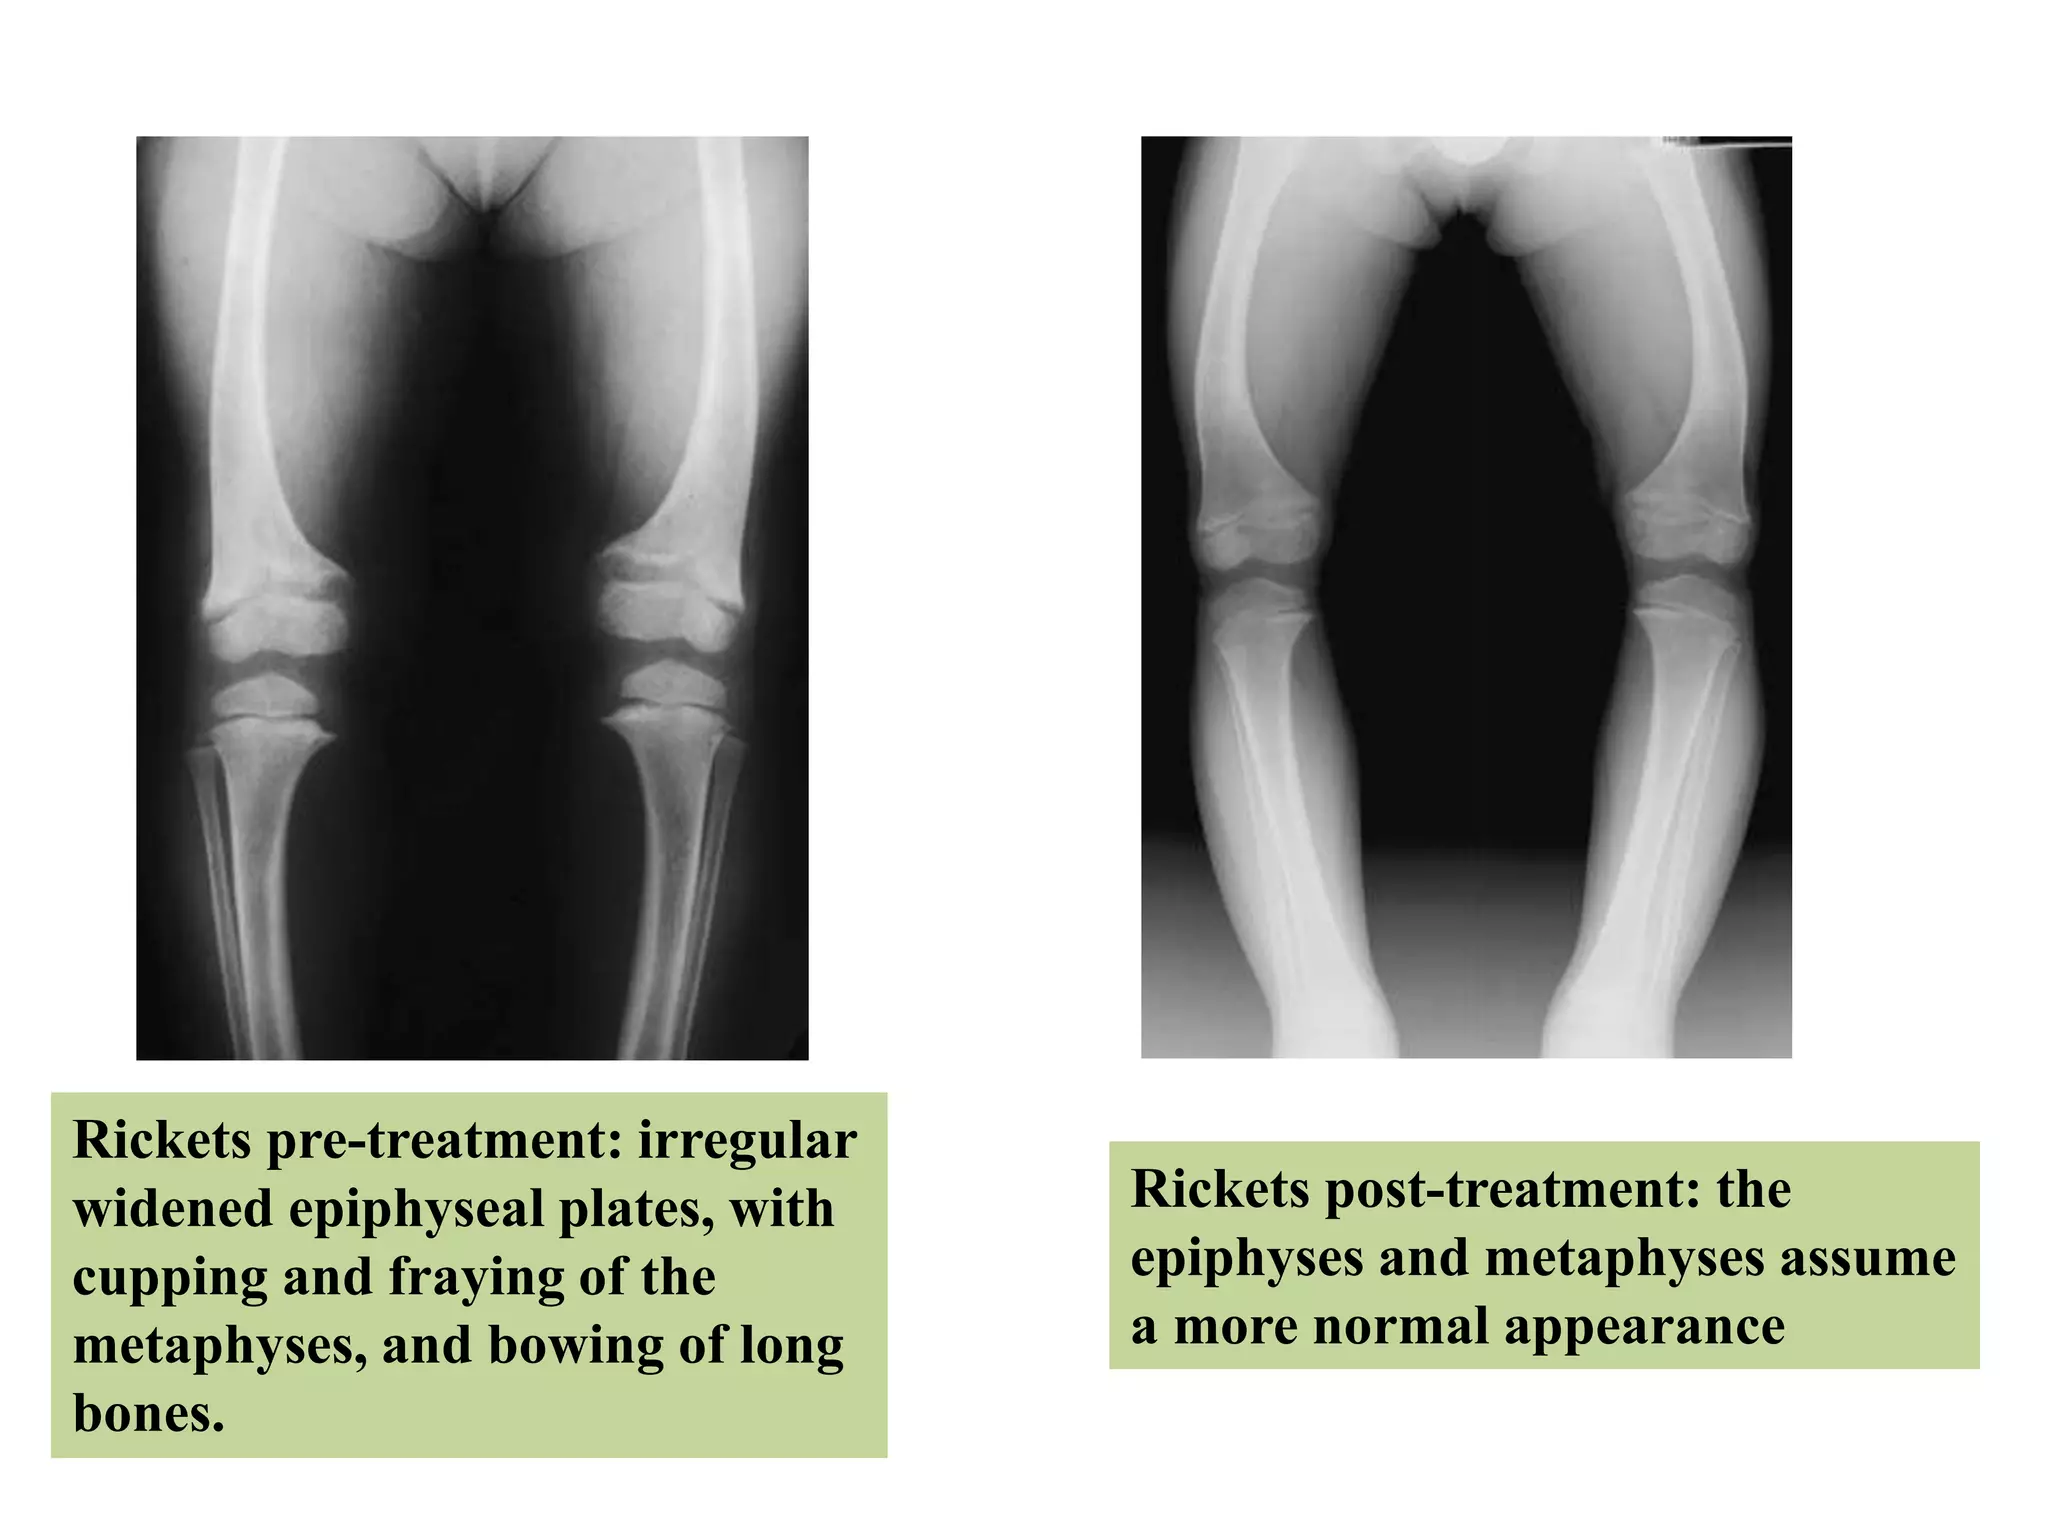

• Earliest radiological sign is

loss of normal zone of

provisional calcification

adjacent to metaphysis.

• Later, metaphyseal margin

becomes indistinct

& frayed.

• Growth plate become

widened.

Rickets pre-treatment: irregular

widened epiphyseal plates, with

cupping and fraying of the

metaphyses, and bowing of long

bones.

Rickets post-treatment: the

epiphyses and metaphyses assume

a more normal appearance